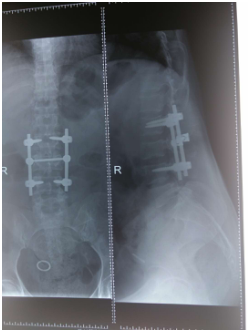

(上圖為患者術(shù)前X片)